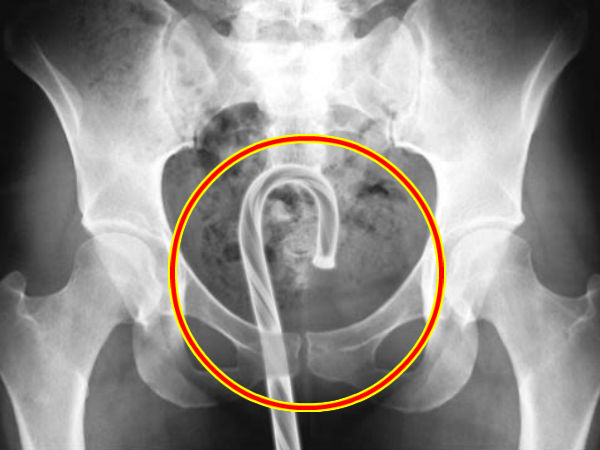

சிகிச்சையின் போது பெண்ணுறுப்பில் மருத்துவர்கள் கண்டெடுத்த 14 விசித்திரமான பொருட்கள்!

சிகிச்சையின் போது மனித உடலில் மருத்துவர்கள் கண்டெடுத்த விசித்திரமான பொருட்கள்!

நமது சிறு வயதில் குழந்தைகள் சிலர் ஸ்லேட் பென்ஸில் கொண்டு விளையாடும் போது மூக்கில் சிக்கிக் கொண்ட நிகழ்வு, காசு விழுங்கி தொடையில் சிக்கிக் கொண்ட நிகழ்வுகள் பல கண்டிருப்போம். ஏன் இந்த தவறை நம்மில் சிலரே கூட செய்திருக்கலாம்.

ஆனால், வயதுவந்த பிறகு... இளைஞர்கள், செக்ஸ் விளையாட்டில் அதிக ஈடுபாடு கொண்டுள்ளவர்கள். போதையில், விசித்திரமான முயற்சியில் தங்கள் அந்தரங்க உறுப்புகளில் கண்ட பொருட்களை சிக்க வைத்துக் கொள்வார்கள். இதுப் போன்ற நிகழ்வுகள் வெளிநாட்டில் அடிக்கடி நிகழ்கின்றன.

அமெரிக்காவில் இதற்கென தனி ஆணையமே இருக்கிறது. அந்த ஆணையம் அவசர சிகிச்சையின் போது மக்கள் உடல் உறுப்புகளில் கண்டெடுக்கப்பட்ட பொருட்கள் என ஒரு பட்டியலை வெளியிட்டிருந்தது. அதில் இருந்து கிடத்தி தகவல்களை தான் இந்த தொகுப்பில் நாம் காணவிருக்கிறோம்...

மனித உடலில் இருந்து சிகிச்சையின் போது கண்டெடுக்கப்பட்ட பொருட்கள் என மருத்துவர்கள் கூறிய இந்த தகவல்கள், அமெரிக்காவின் நுகர்வோர் தயாரிப்பு பாதுகாப்பு ஆணையத்தின் தரவுத்தளத்தில் (U.S. Consumer Product Safety Commission's database) இருந்து அவசர நிலை சிகிச்சைக்கு வந்தவர்கள் பட்டியலில் இருந்து வெளியிடப்பட்டவை ஆகும்.

அவசர சிகிச்சையின் பேரில் தங்களிடம் சிகிச்சைக்கு வந்த ஒவ்வொரு உடல் பாகத்தில் இருந்து மருத்துவர்கள் தாங்கள் எடுத்ததாக கூறியிருக்கும் இந்த தகவல்கள் நிச்சயம் சிலருக்கு ஒரு நிமிடம் தலை சுற்றல் ஏற்படுத்தலாம்.

ஆணுறுப்பில்!

- சிறிய ஸ்க்ரூ

- கூர்மையான பொம்மை பாகம்

- நான்கு அங்குலம் நீளமான இரும்பிலான செக்ஸ் பொம்மை

- பிளாஸ்டிக் ஸ்பூன்

- டொமினோ எனும் விளையாட்டு பொருள்

- பிளாஸ்டிக் ஷாம்பூ பாட்டிலும் சிறு பாகம்

- பேப்பர் கிளிப்

- இணையச்சு ஒயர்

பெண்ணுறுப்பில்!

- திரவிய சோப்பு

- டியோடிரன்ட் மூடி

- பாட்டில் மூடி

- ஆண்குறி ரிங் (செக்ஸ் பொம்மை)

- துருப்பிடித்த இரும்பு கம்பி

- சிலிகான் பந்துகள்

- பந்து

- பைக் ரிஃப்லெக்டார்

- பீரியட் நாட்களில் வைக்கப்பட்ட கருத்தடை பஞ்சு உபகரணம்.

- ஹெட்போன்

- டவல்

- மொபைல்

- மெழுகுவர்த்தி

- லாலிபாப்

மலக்குடல்!